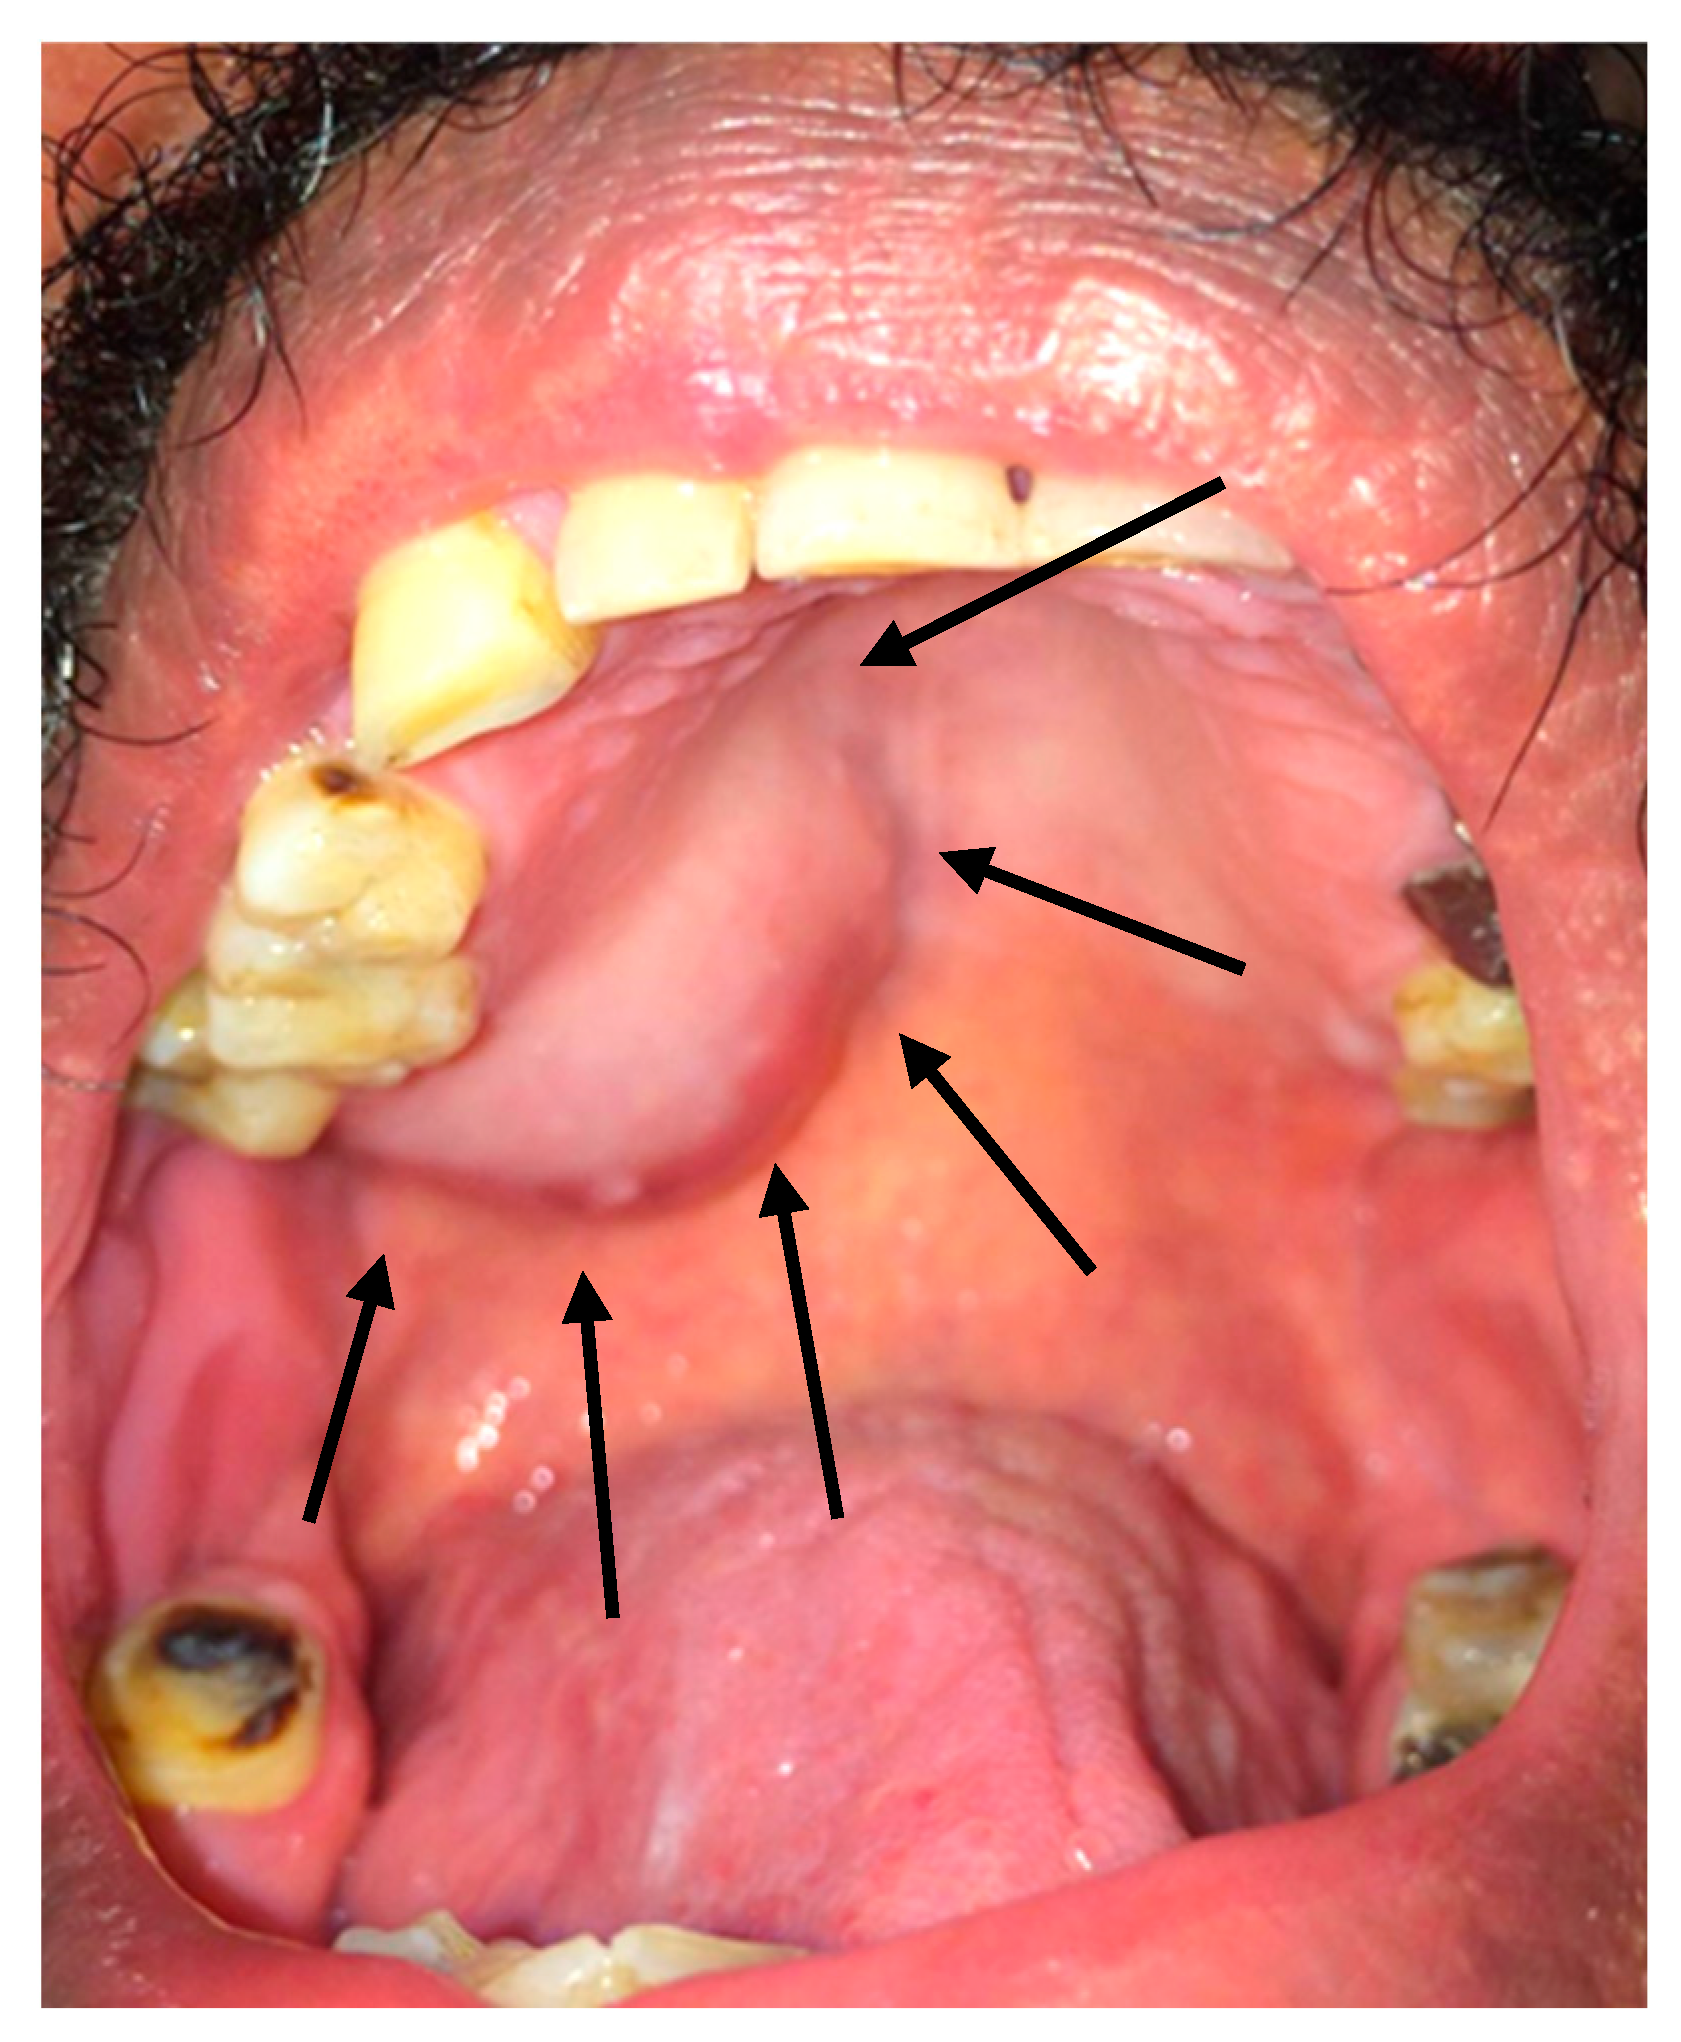

2.2. Clinical Findings